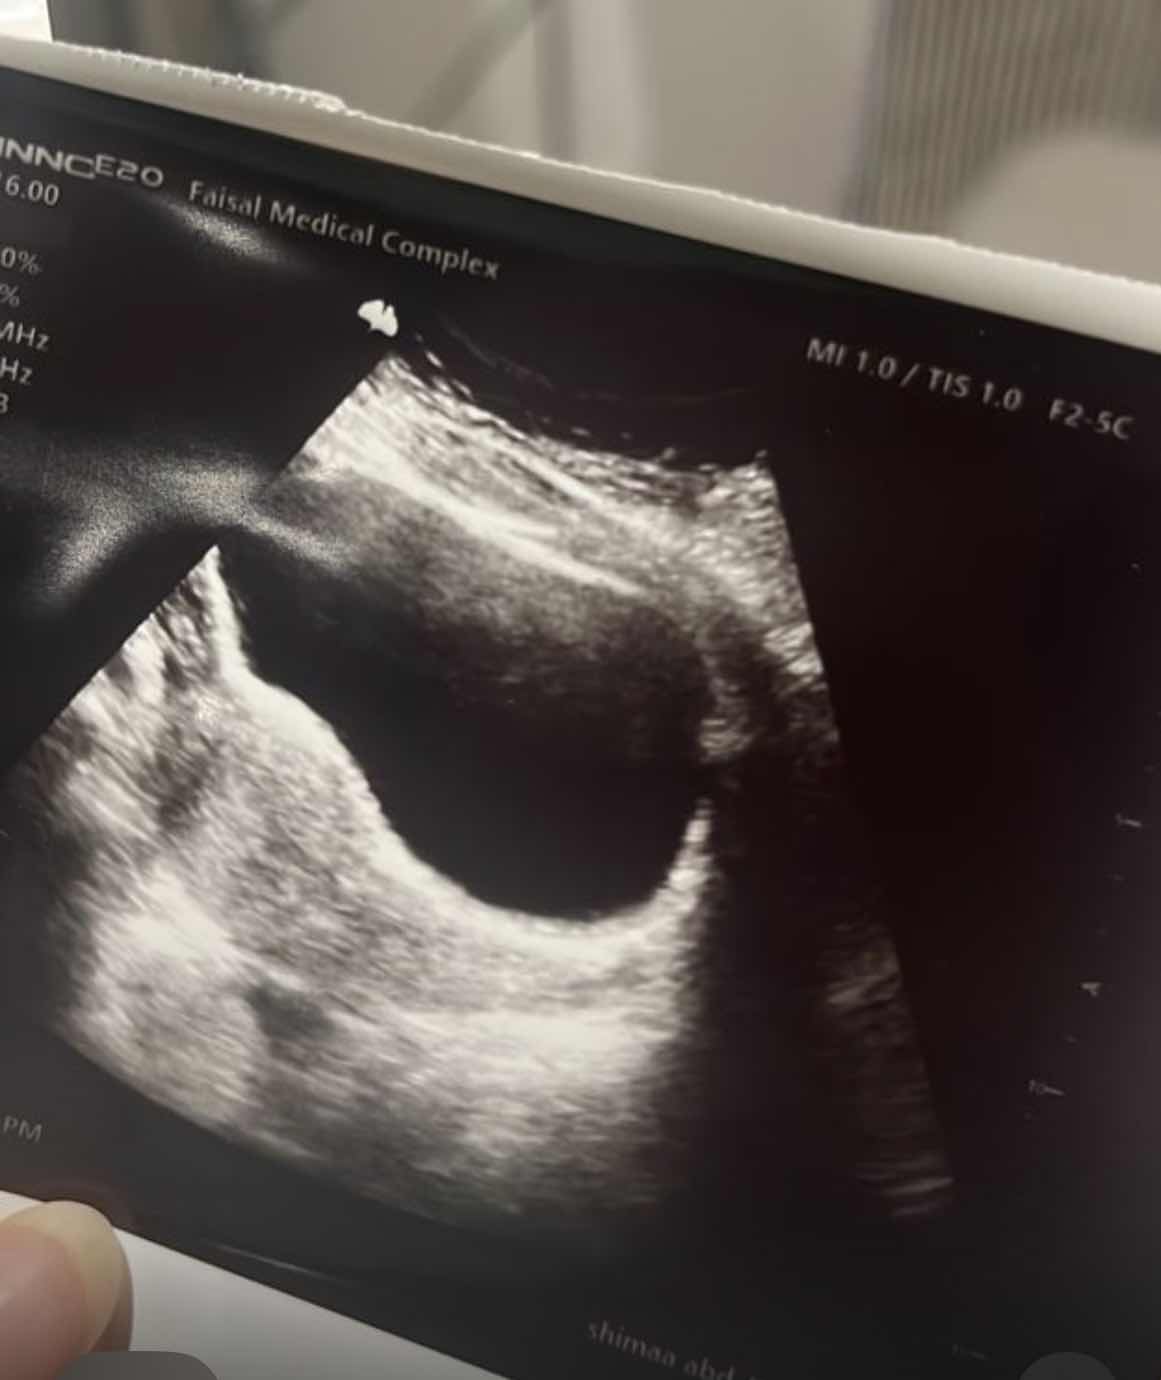

icon 169

لا يظهر كيس حمل في الصورة المرفقة وينصح باعاده السونار في مركز متخصص عن طريق البطن او المهبل اذا لزم ولا يسبب هذا اجهاض 0 2025-12-06T11:42:40+00:00 2025-12-06T11:42:40+00:00

لا يظهر كيس حمل في الصورة المرفقة وينصح باعاده السونار في مركز متخصص عن طريق البطن او المهبل اذا لزم ولا يسبب هذا اجهاض